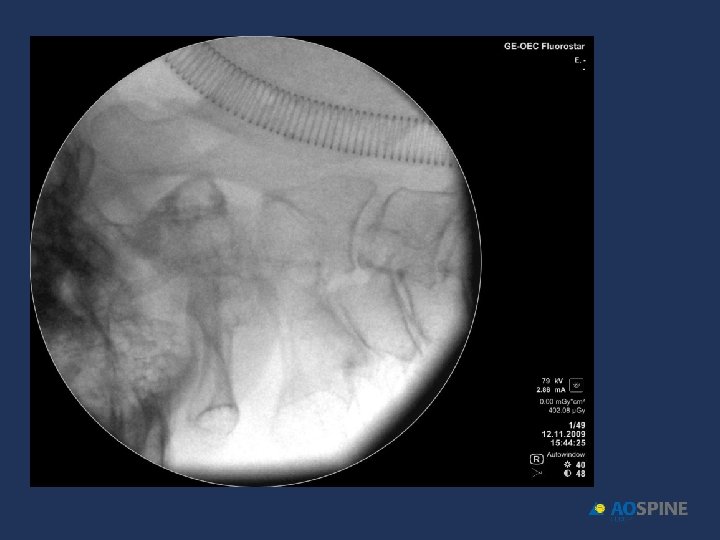

ODONTOID FRACTURES